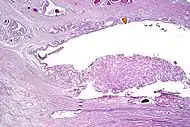

| Non acinar (or mixed acinar/ non-acinar) adenocarcinoma | Ductal adenocarcinoma | 3% to 12.7%[8][notes 1] | ![]() |

||||